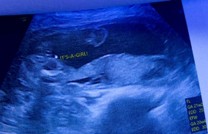

เพศลูกน้อย

แม่ๆรู้เพศลูกอายุครรภ์เท่าไหร่กันคะ

ชัดอยู่ค่ะถ้าน้องให้ความร่วมมือ

น้องอ้าขาโชว์ แล้วไข่โผล่เลยค่ะ🤣 ไม่ต้องลุ้นแล้วค่ะ555